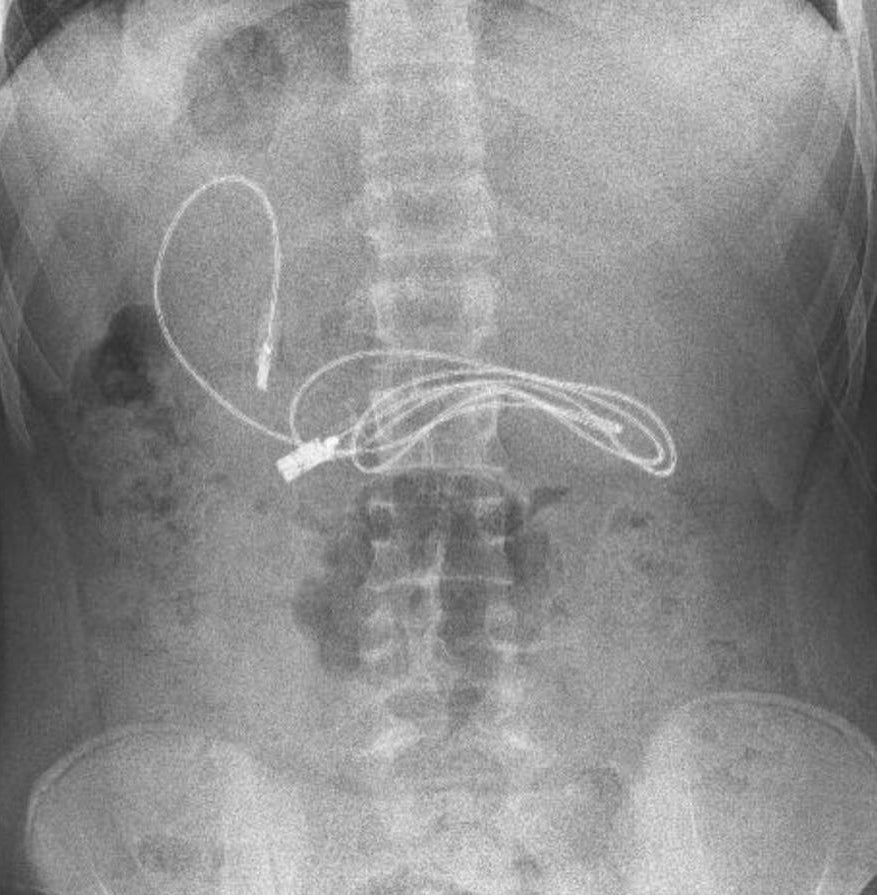

Diyarbakır'da kusma ve bulantı şikayetiyle hastaneye giden 15 yaşındaki erkek çocuğunun çekilen röntgeninde, midesinde şarj kablosu ve toka olduğu tespit edildi.

Bunun üzerine çocuk, ambulans ile Fırat Üniversitesi Hastanesi'ne sevk edildi. Üniversitenin Çocuk Gastroenteroloji Hepatoloji ve Beslenme Bilim Dalı Başkanı Prof. Dr. Yaşar Doğan ve ekibi tarafından yapılan endoskopik işlemle çocuğun midesindeki kablo ve toka başarıyla çıkarıldı.

Ameliyatı gerçekleştiren Prof. Dr. Yaşar Doğan, kablonun bir ucunun ince bağırsağa geçmesi nedeniyle zorlandıklarını ifade ederek, “Hastanın kusma ve karın ağrısı şikayetleri olması üzerine sağlık kuruluşuna başvurulmuş. Orada yapılan incelemelerde hastanın midesinde kablo tespit edilmesi üzerine bize danışıldı. 112 aracılığıyla hastaya gerekli işlemi yapıp yapmayacaklarını bize sordular. Biz de hastayı bize gönderebileceklerini kendilerine ilettik. Hasta bize geldikten sonra ön hazırlık yapıldı ve gerekli olan açlık süresinin ardından hastaya endoskopik işlem yapıldı. Endoskopik işlemle midedeki kablo çıkarıldı. Kabloyu çıkarırken açıkçası zorlandık, çünkü kablonun bir ucu ince bağırsağa geçmişti. İşlem başarılı bir şekilde sonlandırıldıktan sonra hasta sağlıklı bir şekilde evine gönderildi” dedi.